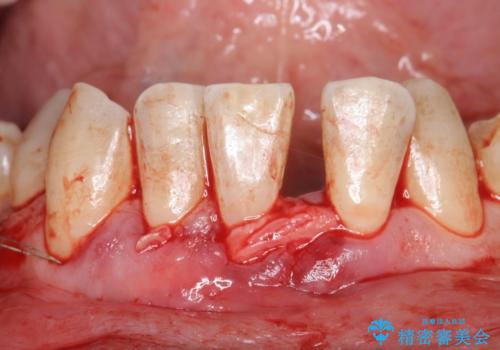

- 矯正前に下顎前歯の歯肉退縮の改善と予防のために歯肉移植を行った症例です。

上顎口蓋部から結合組織を採取し、下顎前歯部に移植しました。